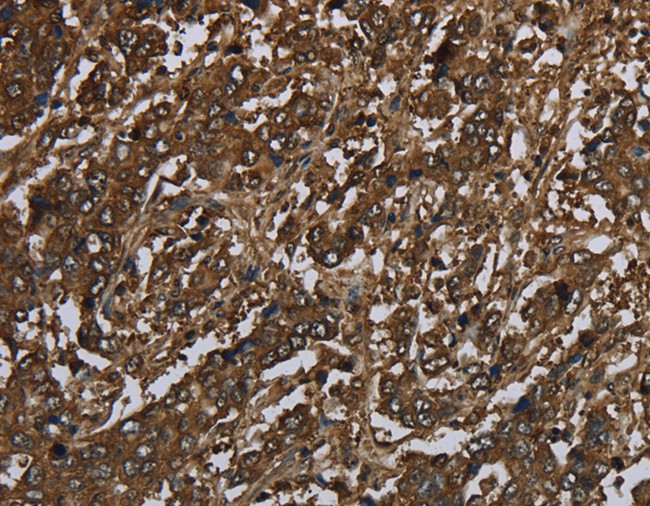

IHC (Immunohiostchemistry)

(Immunohistochemistry of paraffin-embedded Human liver cancer using GLO1 Polyclonal Antibody at dilution of 1:60)